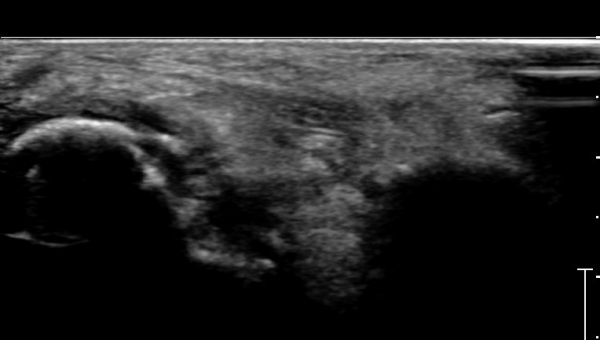

Á¾°ñ Àü¹æµ¹±â Ⱦ´Ü¸é°Ë»ç»ó Àü¹æµ¹±â ¿ÜÃø°ú ³»ÃøºÎ °ß¿­°ñÀýÀÌ °üÂûµÈ´Ù(»çÁø 3).